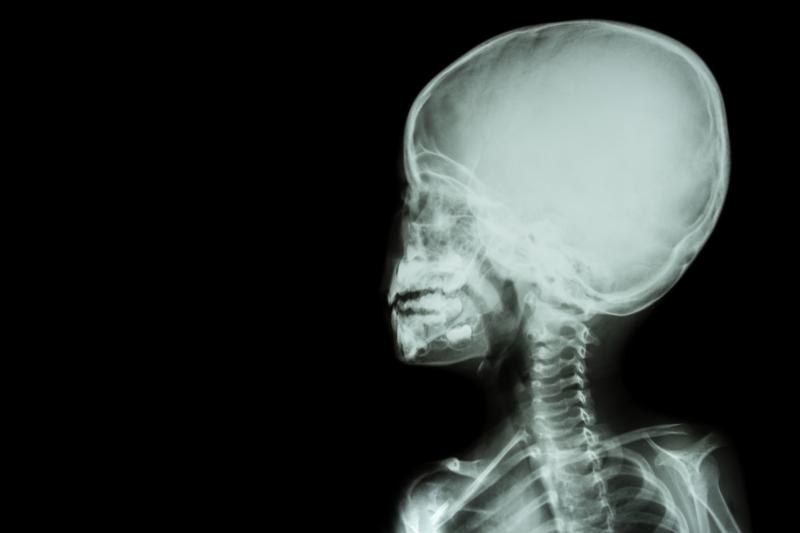

Neonatal brain injuries may have short-term impact on infant neurodevelopment, particularly in terms of motor skills and behaviour during childhood, a recent study has found. Using magnetic resonance imaging (MRI), along with a standardized scoring system, may be an effective measure to monitor for such injuries.

The study included 112 neonates born very preterm (<32 weeks of gestation), in whom brain injury was assessed through a neonatal MRI and graded using the Kidokoro Score. Participants were followed-up at 2 years of age (corrected for prematurity) and at 10 years (uncorrected), during which standardized cognitive and motor function tests were administered.